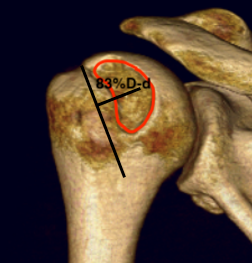

Glenoid track is 83% of glenoid width of intact glenoid

- subtract any glenoid bone loss

- 83%D - d

- this distance from medial rotator cuff foot print on humeral head

- engaging or off track lesion: Hill Sachs medial to medial border of this line

- non engaging or on track lesion: Hill Sachs medial border lateral to medial border of this line